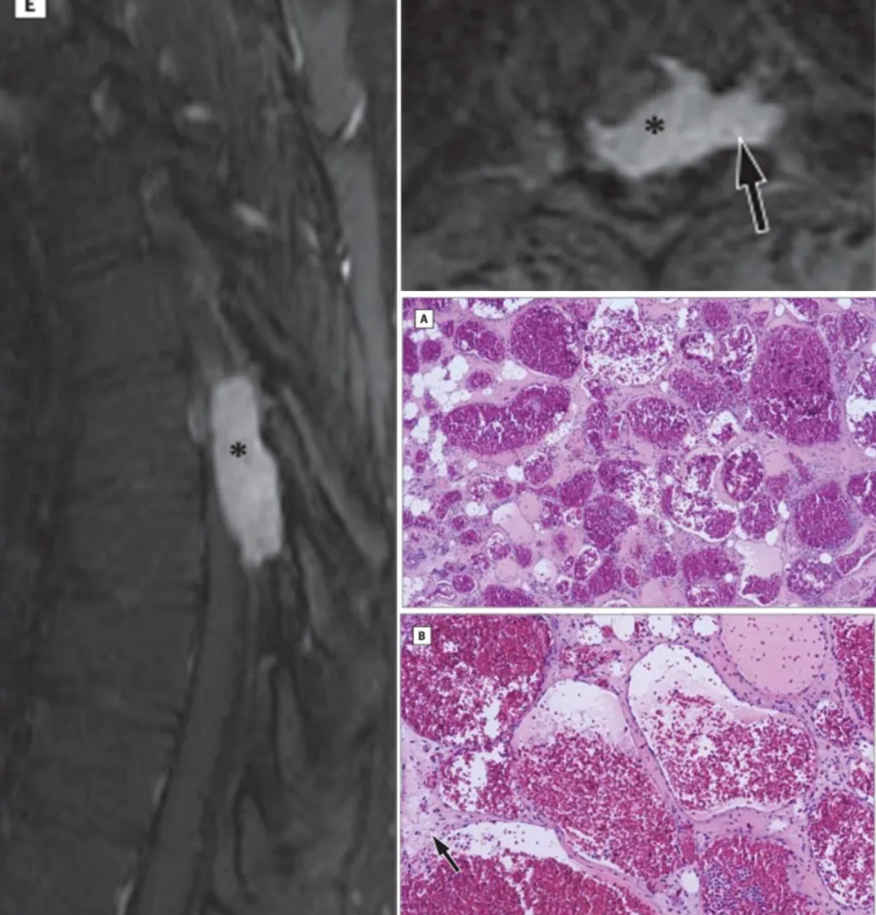

典型影像、病理学特征:MRI见平行脊椎长轴生长的两头尖锐的纺锤形改变(毛笔尖征)(左),由于脊柱背侧硬膜外间隙上下连贯,内含有丰富的疏松的脂肪组织,因此相对空间较大、扩张阻力小,同时可于椎间孔蔓延(右上)。病理切片(HE染色):44×低倍放大镜下的病理照片,显示病变内有紧邻的薄壁血管空间,内充满血液(右中)。110×高倍的放大镜下,显示血管空间的平坦内皮衬里,以及不规则纤维间隔中的小脂肪细胞灶(箭头所指)(右下)。